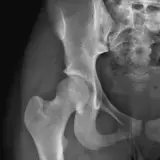

Over 2,100 interactive radiology cases, curated by radiologists for your level of training. Scroll, window, and view cases full screen — just like on PACS. Click linked findings in each writeup to jump straight to them on the image. Cases include sample reports, a focused discussion section, original illustrations, and videos.

Casos totalmente interativos com as ferramentas que você espera em um PACS — rolagem, ajuste de janela, zoom, movimentação, medidas, ROIs e modo de tela cheia.

Anotações detalhadas destacam os achados principais diretamente nos casos. Clique nos achados vinculados nas descrições dos casos para ir ao local exato no exame.